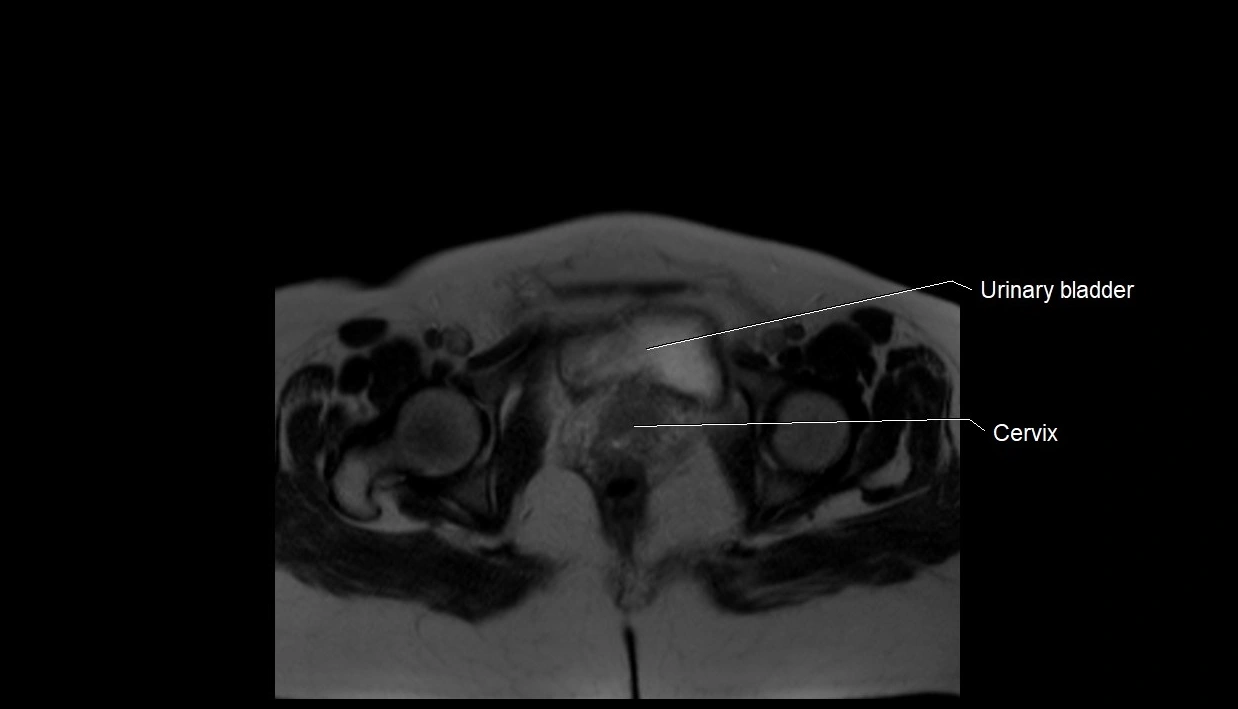

MRI Appearance

T2 HASTE (T2 GRE):

• Amniotic fluid shows very bright hyperintense signal

• Provides natural contrast against fetus and placenta

T1 GRE:

• Amniotic fluid shows low signal intensity (dark)

• Hemorrhage, infection, or proteinaceous content may cause focal or diffuse high signal intensity

MRI image

image